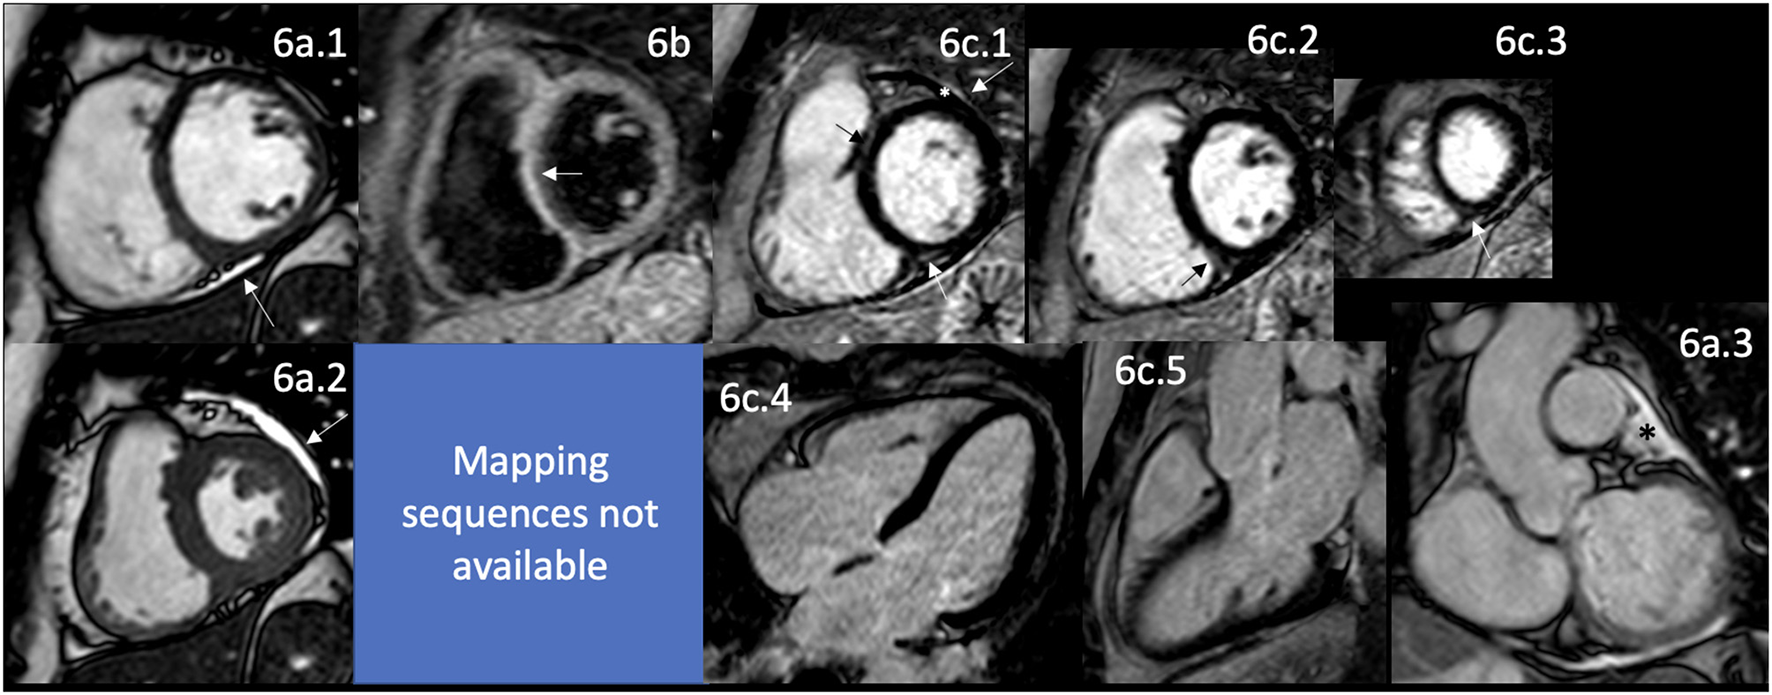

Figure 5

CMR findings in SSc. A panel figure demonstrates varying findings by a comprehensive CMR study at 1.5 Tesla scanner of SS. (a) SSFP sequence still cine images in short-axis view at the mid-ventricular level in end-diastole (a.1) and end-systole (a.2) shows normal global and regional functions of both ventricles, LVEF 57% and RVEF 56%. (b.1) T2-W STIR sequence in short-axis view at the mid-ventricular level of normal myocardium and myocardial/skeletal muscle ratio. (b.2) T1 mapping with a native T1 of 998 ms (mildly increase) and a calculated ECV of 32% (mildly increase). (c.1–5) LGE PSIR sequence. (c.1–3) Short-axis views at basal (c.1), mid (c.2), and apical (c.3) levels, and long-axis views in 4-chambers (c.4) and 3-chambers (c.5). The arrowheads in these images show areas of focal fibrosis as mid-wall LGE of the anteroseptal segment in (c.1) and the subepicardium of the inferior segment in (c.1–3) in the basal and mid anterolateral segments in (c.4) and subendocardial in the LV apex in (c.5). In addition, the same set of images shows LGE of the pericardium without effusion (arrow), suggestive of pericardial inflammation. CMR, cardiovascular magnetic resonance; SS, systemic sclerosis; SSFP, steady-state free precession; LVEF%, left ventricular ejection fraction; RVEF%, right ventricular ejection fraction; T2-W STIR, T2-weighted short-tau inversion recovery; ECV, extracellular volume; LGE, late gadolinium enhancement; PSIR, phase-sensitive inversion recovery.

Cardiac involvement is reported high in histopathological reports as in CMR studies, reaching 75–80% of patients with this disease (162). The cardiovascular clinical presentation most commonly includes the lungs with nonspecific interstitial pneumonitis, interstitial pneumonia, and PH (163). In the heart (Figure 1), both forms of SSc (164) includes pericardial inflammation (Figure 5c.1–5) with clinical presentation of pericarditis in 10–20% of cases (165), pericardial effusions with fibrosis (Figure 5c.1–5) and thickening that reaches constrictive pericarditis, and myocardial involvement, with edema (Figure 5b.1) presenting as myocarditis that could be even fulminant (164, 166), and fibrosis (Figure 5c.1–5), which characteristically affects both ventricles (166, 167) that progresses to conduction disturbances, such as conduction blockades, atrioventricular or intraventricular in 28–52.8% of cases on resting ECG or 38–56% of cases on 24-h Holter monitoring (168) or ventricular arrhythmias; and progressive cardiac dilatation and systolic-diastolic dysfunction ending up in HF (164). Diastolic dysfunction is the most common finding, reported in 30 (165) to 44% of cases (169), may be related to the broader use of Echo as the initial, and sometimes, a unique diagnostic tool for the evaluation of the involvement of the heart in this disease. Some reports also describe VHD (167).

CMR evaluation of these patients allows for assessing the right-sided heart. It shows that, even in the absence of PH, there are hemodynamic abnormalities manifested as right atria and ventricle enlargement, which increases progressively along with the vascular resistance and the pulmonary artery systolic pressure (PASP) with the establishment of PH and finally with RV dysfunction in 5–10% of cases (165, 169). CMR cannot measure the PASP directly; however, some indirect findings orient to the presence of PH and correlate well with the invasive measurement of PASP; one important finding is the systolic shift of the interventricular septum toward the LV, when this finding is observed in CMR the PASP is usually higher than 67 mmHg; therefore, the patient is with at least moderate PH (173).

Interestingly, even with the detection of myocardial edema (Figure 5b.1), focal and diffuse fibrosis (Figure 5c.1–5) by CMR, and the presence of a certain degree of LV dysfunction present in 5% of cases (165), the clinical presentation of HF is uncommon in these patients, with only 5% manifesting the same (174). LGE in SSc has a typical pattern of non-ischemic cardiomyopathy (Figure 5c.1–5), with non-coronary distribution as in other ADs, with a linear mid-wall distribution, even in subclinical and early-stage cases; without significant impairment of cardiac function at that time (175) (Figure 5a.1,2). As in ischemic patients with a higher LGE burden, ventricular arrhythmias have a stronger association, supporting the hypothesis of a fibrotic substrate for this kind of rhythm disturbance. According to the SAnCtUS score, the significant T2-STIR myocardium/skeletal muscle ratio (>2.3) and the presence of more than 5% of LGE of the LV mass can predict the development of potentially life-threatening ventricular arrhythmic events (176).

T1 mapping and ECV values are significantly higher in patients with SSc than in healthy controls (Figure 5b). In addition, a higher burden of diffuse myocardial fibrosis measured by mapping techniques, higher native T1 value (Figure 5b.2), and increased ECV have been associated with more severe interstitial lung disease (177). The potential role of this technique in avoiding the additional risks and costs of using the current gold standard method, the endomyocardial biopsy (178), remains unclear. Still, well-designed studies are helping to answer that question correctly.

The UK Systemic Sclerosis Study Group proposed a comprehensive algorithm that classifies patients as asymptomatic, at-risk, and symptomatic for cardiac complications, including the standard assessment including patient history, blood pressure, lipid profile, and HbA1c, ECG, Echo, a core set of parameters to be measured at each Echo and laboratory parameters; the follow-up intervals are determined by the risk categorization. In this context, CMR is recommended in a more individualized analysis, depending on the clinical manifestation of each patient independent of their risk categorization in the algorithm (179). See Table 5 for detailed CMR offerings to SSc and Table 1 for pros and cons over other imaging modalities.